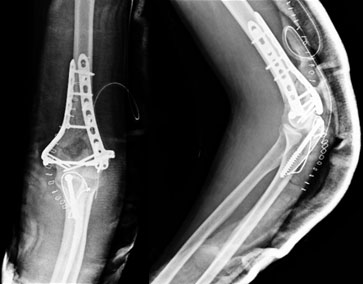

After surgery

In the surgery the fragments were brought back into place and a congruent joint surface was restored. The fracture was fixed using locked plate on both the columns. The Olecranon was osteotomized for getting a better view of the joint, which was later fixed with a tension band. |

1 ½ year post surgery

The fracture healed well as seen in the xrays. The implants are still holding well. We do not recommend implant removal routinely unless the implant is causing any trouble. |